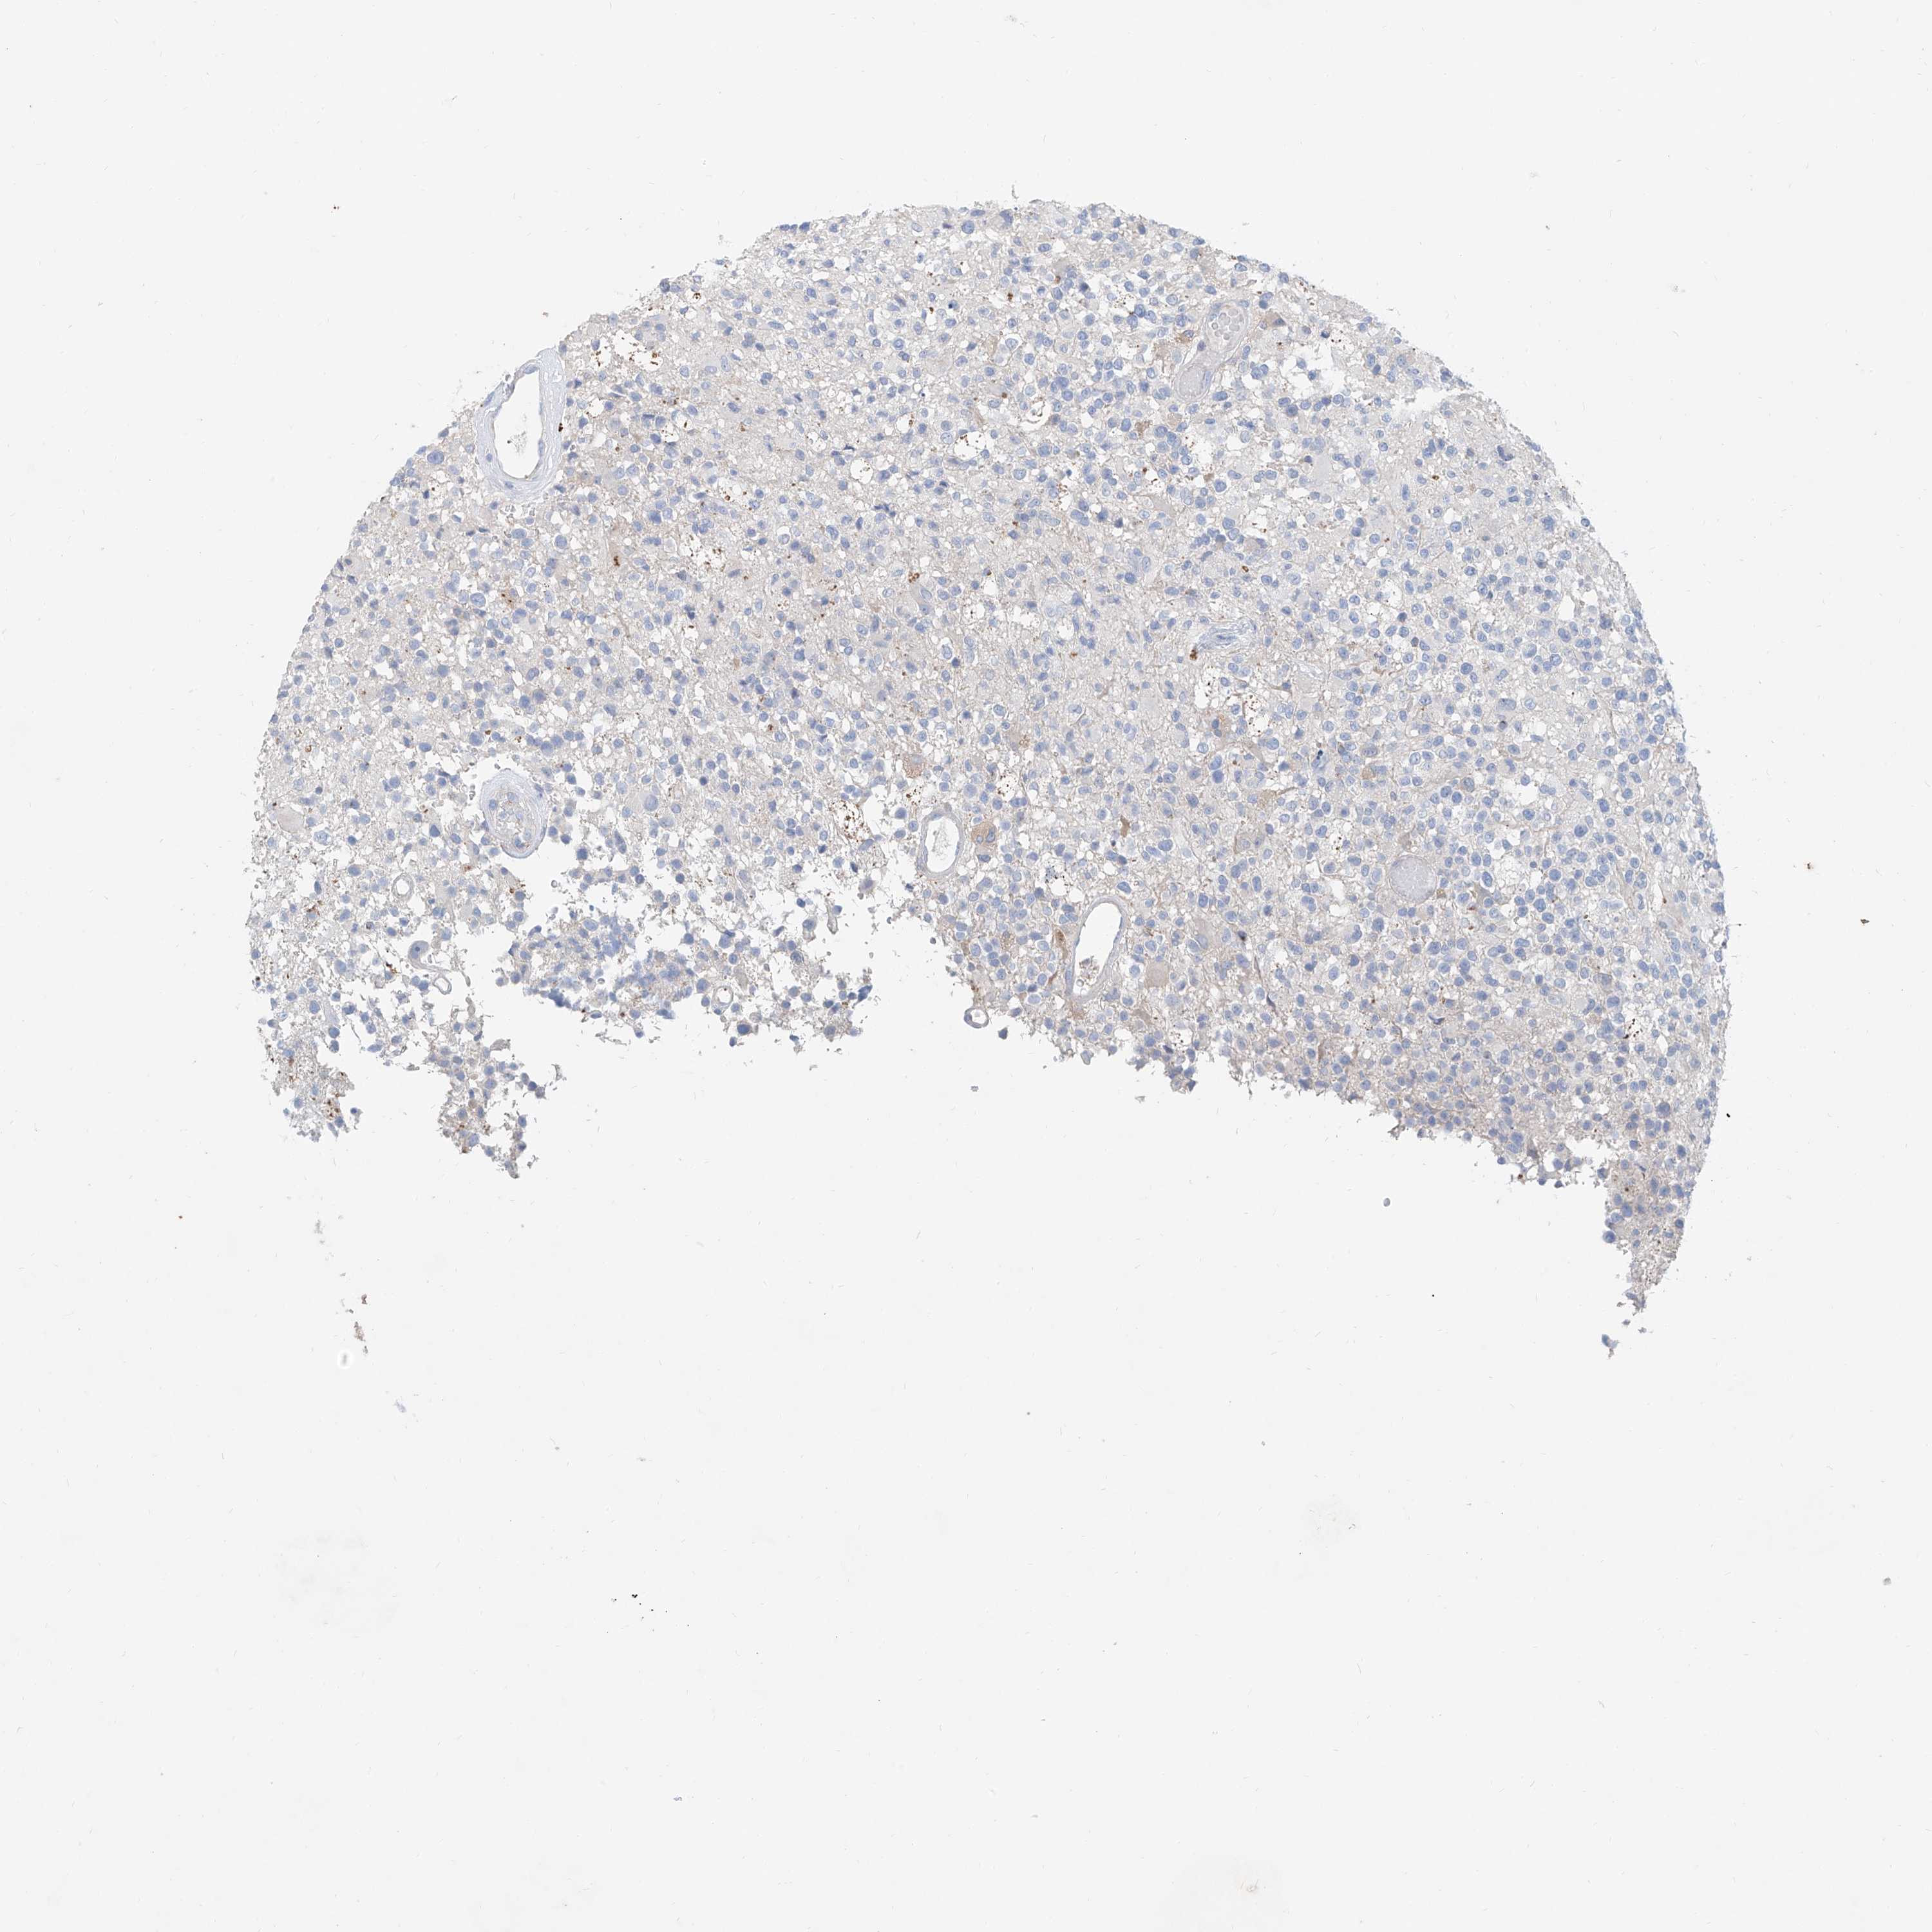

GLIOMA - Protein expressioni

A mouse-over function shows sample information and annotation data. Click on an image to view it in a full screen mode. Samples can be filtered based on level of antibody staining by selecting one or several of the following categories: high, medium, low and not detected. The assay and annotation is described here.

Note that samples used for immunohistochemistry by the Human Protein Atlas do not correspond to samples in the TCGA dataset.

Antibody stainingi

Antibody staining in the annotated cell types in the current human tissue is reported as not detected, low, medium, or high, based on conventional immunohistochemistry profiling in selected tissues. This score is based on the combination of the staining intensity and fraction of stained cells.

Each image is clickable and will lead to virtual microscopy that enables deeper exploration of all samples and also displays staining intensity scores, fraction scores and subcellular localization as well as patient and tissue information for each sample.

Antibody HPA029642

Antibody HPA029643

Glioma, malignant, Low grade